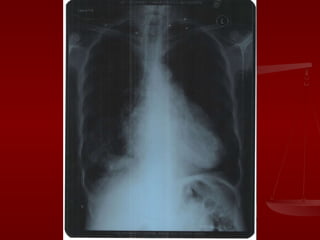

On investigation Routine investigations ECG CXR PA view USG abdomen D- dimmer assay PFT

On investigation Routineinvestigations ECG CXR PA view USG abdomen D- dimmer assay PFT